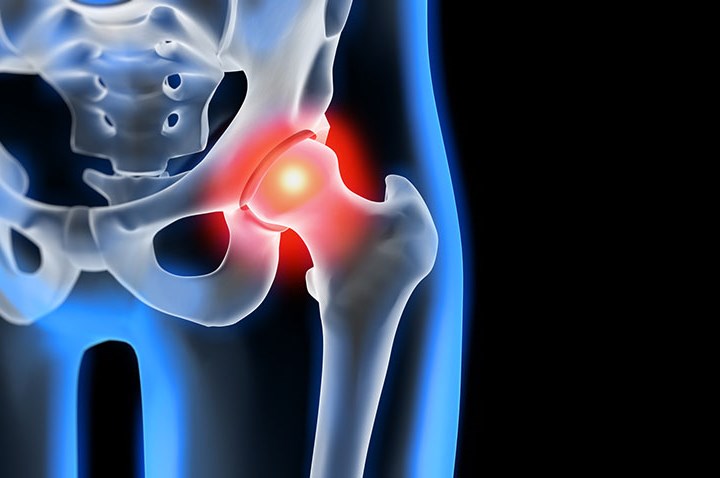

Złamanie szyjki kości udowej to uraz w obrębie stawu biodrowego, który po upadku uniemożliwia obciążenie nogi i powoduje silny ból w pachwinie lub biodrze. Dotyczy osób starszych z osteoporozą, a u młodszych jest skutkiem urazu wysokoenergetycznego. Złamanie powstaje w szyjce łączącej głowę kości udowej z trzonem i leży wewnątrz torebki stawowej. Zaburza dopływ krwi do głowy kości udowej i zwiększa...